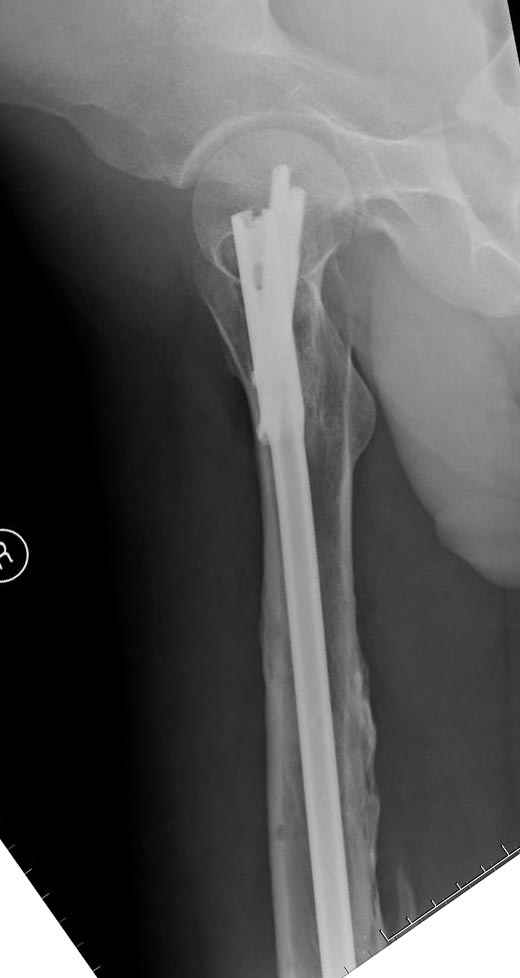

если первые 4 месяца послеоперационного периода проходил без проблем, но на 5 месяце появились боли в дистальном отделе бедра и температура, т.е. симптомы медуллярного инфицирования (рис №3, №4).

Замена реконструктивного штифта “Custom made Nail” с антибиотиком (рис №5, №6),

после промывки канала с рассверливанием внутреннего кортекса, через 4 недели антибиотический штифт удалили, оспалителный процесс остановлен и бедро сросся.